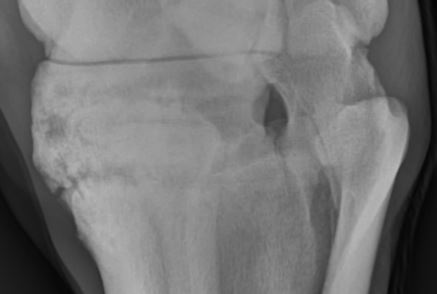

Så här ser Dingos has ut nu:

Hovbensfrakturen är helt läkt och glidlederna i hasen har vuxit samman mycket mer än vad de hade gjort sist vi röntgade! Det är visserligen fortfarande en liten del som inte är helt sammanvuxet och det är därför som han haltar i trav, men han är åtminstone haltfri i skritt. Han fick en kortisonspruta och förhoppningsvis lugnar den inflammationen och smärtan så pass att han inte känner av det så tydligt.